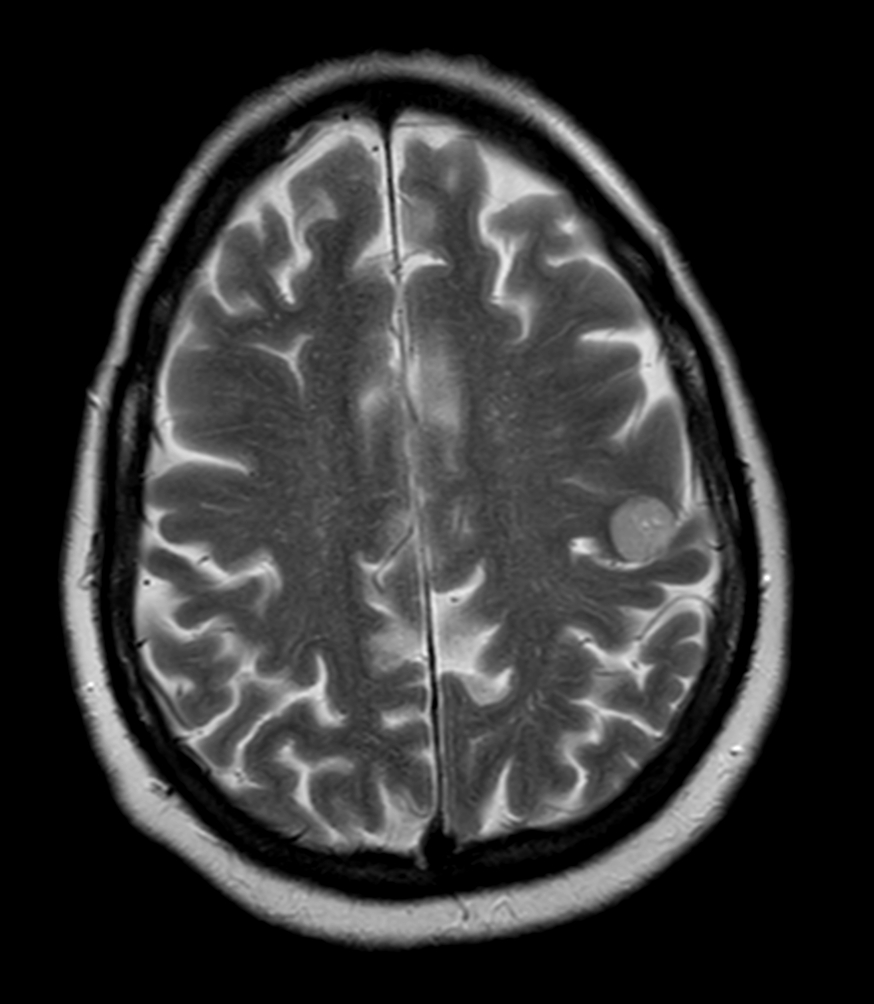

Female with one metastasis of pulmonary cancer underwent MRI simulation in the radiotherapy positioning mask on Ingenia MR-RT 1.5T before stereotactic radiation therapy with 25 Gy in 3 fractions.

Axial T2w TSE